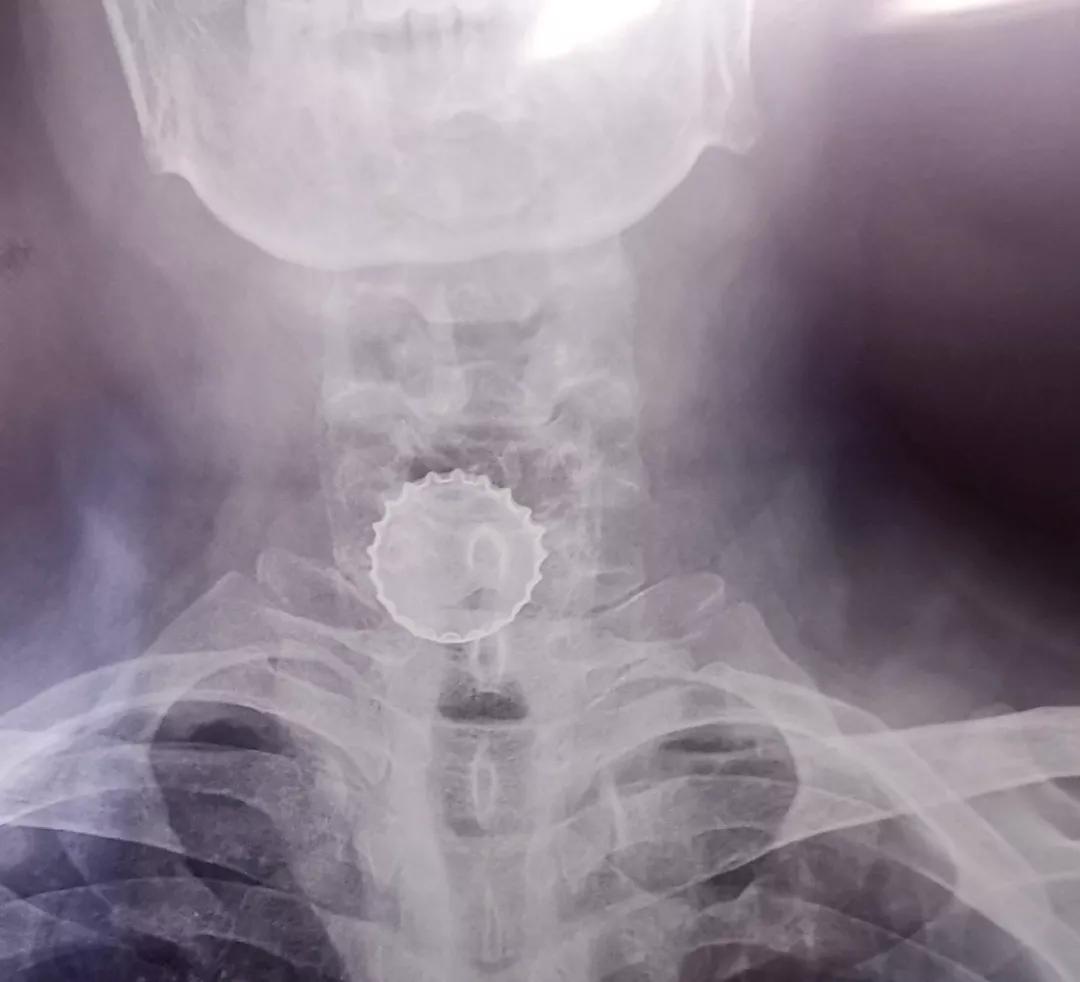

医生在了解朱先生的伤情后,为其进行了胸部X光检查,检查结果显示在朱先生咽喉部位有一规整的圆形异物,但当地医院没有能力为其取出,折腾到半夜后,朱先生暂时先回家休息,9日一早又换了一家医院寻求取出异物的治疗。结果医生了解其病情和相关检查结果后,初步判断朱先生吐下的是一只瓶酒瓶盖,由于瓶盖边缘光滑锐利,当地医院担心在为其取出瓶盖过程中,锋利的边角会划伤食道和气管,严重可能需要开胸手术才能取出异物,所以建议朱先生前往综合性大医院处置。几经折腾后,9日下午朱先生抱着一丝希望辗转来到新桥医院耳鼻咽喉科求助。

医生在了解朱先生的情况后,尝试为其进行电子鼻咽喉镜检查,经过初步探查,医生诊断患者咽喉部的异物确定为一只啤酒瓶盖,已卡在朱先生食道口。具有丰富咽喉部异物探取经验的刘庆顺医生,沉着冷静地取来异物夹,小心翼翼地夹住瓶盖边缘,然后在确保瓶盖被紧紧夹住的情况下,轻缓地将瓶盖一点点取出。